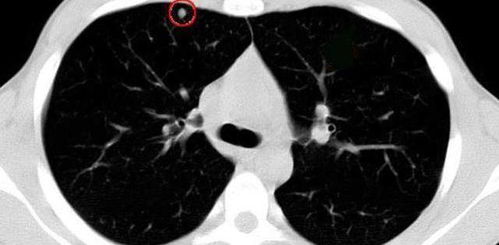

桑黄对结节患者有效吗

结节性硬化症是临床常见疾病。这种疾病的出现会在一定程度上影响患者的健康,严重的患者甚至会出现精神问题。所以发现结节性硬化症要尽早治疗,以免延误病情,造成更大的危害。中医可以治疗结节性硬化症吗?